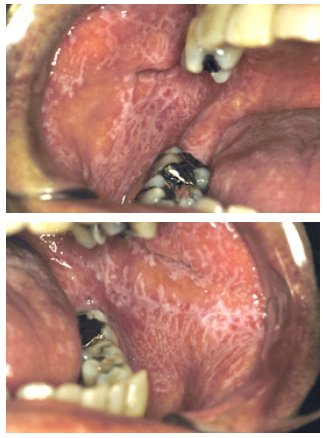

Lichen planus in de mond wordt meestal gekenmerkt door fijne, licht verheven witgrijze lijntjes. Vrijwel altijd gaat het om meerdere plekjes, vaak in een min of meer symmetrisch patroon. Het kan zich ook voordoen als een meer rode afwijking waarin soms één of meer zweertjes kunnen voorkomen.

In de mond komt lichen planus voornamelijk voor op het slijmvlies van de wang en in mindere mate ook dat van de lippen en de tong. Niet zelden is ook het tandvlees er bij betrokken.

Lichen Planus van het wangslijmvlies